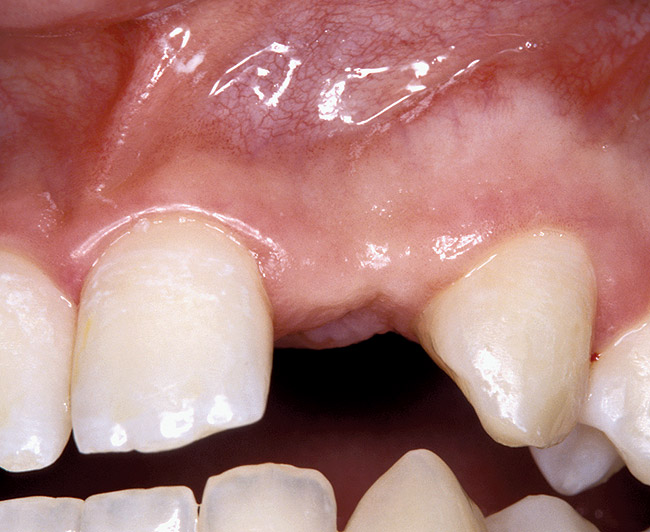

Periapical radiographs were taken to help determine the mesial-distal inclinations of the adjacent tooth roots (Figure 1). The radiographs revealed a serious issue, convergent roots for the right canine and right central, which eliminated that area as a potential implant-receptor site. The space between the left central and canine teeth was minimal, although the roots were relatively parallel. Clinical examination (manual palpation of the root eminences superiorly to the vestibule on the right side) confirmed the root convergence (Figure 2). The flat, wide zone of the keratinized tissue and lack of interdental papilla was evident for the missing right lateral incisor. There was a marked difference in clinical appearance for the left lateral, which could impact the eventual plan of treatment (Figure 3). Other significant clinical findings included bilateral facial bone concavities, which existed as a result of the congenitally missing tooth roots. As a diagnostic cue to the underlying bone topography, it is important to follow the demarcation between attached and unattached gingival tissue, and note the crestal width of the available keratinized tissue (Figure 4).

Before the day of surgery, the patient was seen by the orthodontist for the removal of the orthodontic brackets. The patient still was not pleased with the position of the two centrals, and it was determined that this would be addressed after implant placement (Figure 26). The anatomical variations of the crestal tissue and lack of interdental papilla can be appreciated in the close-up views of the right and left sites (Figure 27 and Figure 28). There were no surprises on the day of surgery as all of the decisions were made during the planning phase, before the scalpel ever touched the patient. The occlusal view of the CT 3D model revealed the wider alveolar ridge on the right side and thinner crest on the left side (Figure 29). This was confirmed when the full-thickness mucoperiosteal flaps were elevated, and the underlying bone revealed (Figure 30). The tooth-borne templates were designed to facilitate the drills and drilling sequence specific to the diameters of the predetermined implants (Figure 31). Each template contained an embedded 5-mm long stainless steel tube, which was approximately 0.2-mm wider than each drill (just wide enough to allow for the drills to rotate freely). Once positioned over the natural teeth, the template was secure and offered precision accuracy in transferring the implant locations from the original software-designed plan, allowing the potential for internal and external irrigation (Figure 32).

Figure 26  VIRTUAL PLANNING AND SURGERY Before implant surgery, the orthodontic brackets were removed, revealing the position of the centrals, and the anatomical variations of the crestal tissue and lack of interdental papilla.

Figure 26

Figure 27   VIRTUAL PLANNING AND SURGERY Before implant surgery, the orthodontic brackets were removed, revealing the position of the centrals, and the anatomical variations of the crestal tissue and lack of interdental papilla.

Figure 27

Figure 28   VIRTUAL PLANNING AND SURGERY Before implant surgery, the orthodontic brackets were removed, revealing the position of the centrals, and the anatomical variations of the crestal tissue and lack of interdental papilla.

Figure 28